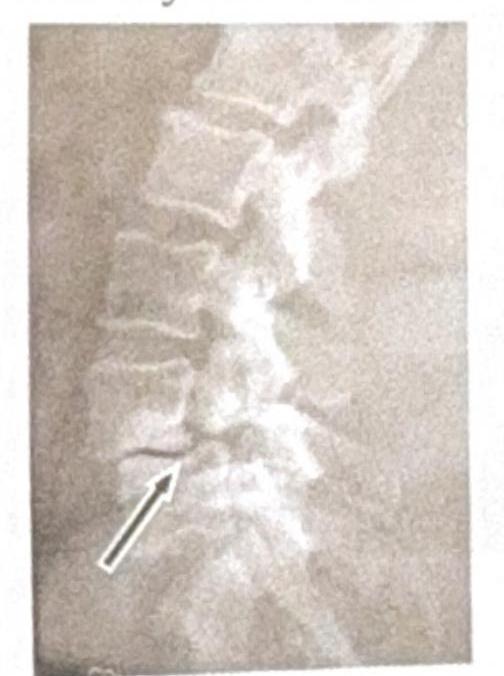

Identify the condition shown in the image:

Explanation: ***Spondylolysis*** * The image shows a **break in the pars interarticularis** of a vertebra, indicated by the arrow, which is characteristic of spondylolysis. * This condition is a **stress fracture** or defect in the pars interarticularis, a bony segment connecting the superior and inferior articular facets. *Renal osteodystrophy* * Renal osteodystrophy refers to a spectrum of **bone abnormalities** that occur in chronic kidney disease, not a specific vertebral fracture pattern. * It typically involves features such as **osteomalacia**, **osteitis fibrosa cystica**, or **osteoporosis**, which are not directly depicted as a fracture in this image. *Spondylolisthesis* * Spondylolisthesis is the **anterior slippage** of one vertebral body over another, which can be caused by bilateral spondylolysis but is not directly shown as a slip in this specific image. * The image distinctly highlights the **fracture line** itself, rather than the displacement of the vertebral body. *Tuberculosis (TB)* * Spinal tuberculosis (Pott's disease) typically presents with **destruction of vertebral bodies**, disc space narrowing, and often a **paravertebral abscess**. * The image does not show these features; instead, it demonstrates a clear **bony defect** in the pars interarticularis.